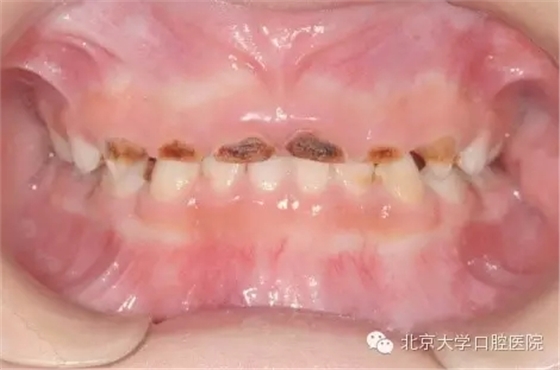

全身麻醉下兒童牙齒治療是一項(xiàng)針對(duì)在口腔醫(yī)學(xué)臨床工作中難于對(duì)牙科恐懼癥患兒、低齡及智障兒童實(shí)施常規(guī)口腔診療的特色技術(shù)項(xiàng)目。從1999年開(kāi)始,北京大學(xué)口腔醫(yī)院兒童口腔科和麻醉科相互協(xié)作在國(guó)內(nèi)率先開(kāi)展該治療技術(shù)。近二十年來(lái),北大口腔醫(yī)院兒科已建成了設(shè)備先進(jìn)的全麻治療室,累計(jì)完成全麻下牙齒治療患者數(shù)千例,使該技術(shù)成為北大口腔醫(yī)院特色醫(yī)療技術(shù)之一。該治療技術(shù)優(yōu)點(diǎn)是在一次治療中醫(yī)生可以高質(zhì)高效地完成全口所有需進(jìn)行的治療工作,特別適用于配合能力差,治療需要量大的患兒。

全身麻醉下的牙齒治療是對(duì)已經(jīng)出現(xiàn)齲壞,牙髓根尖病變的牙齒進(jìn)行治療,是“亡羊補(bǔ)牢”治療本身并沒(méi)有預(yù)防再患齲的作用,而培養(yǎng)孩子良好的口腔衛(wèi)生習(xí)慣才能起到防患于未然的作用,這需要家長(zhǎng)在日常生活中與孩子一起努力。